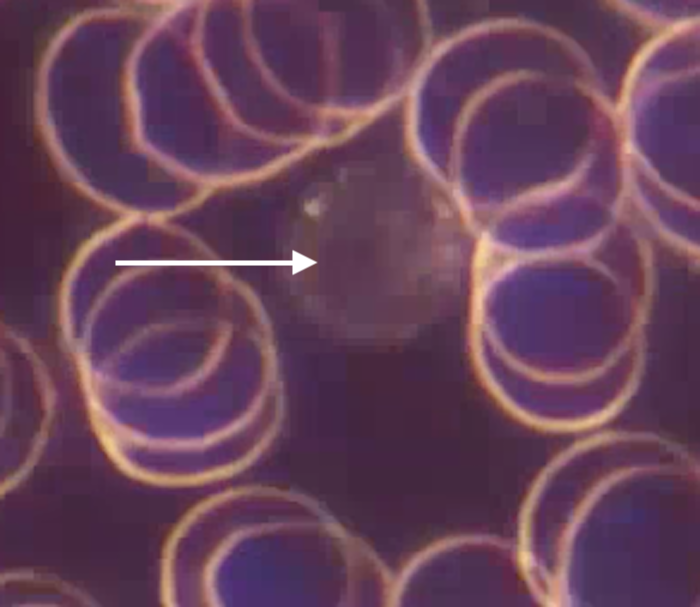

Most of the cells you see in live blood analysis are red blood cells — the smooth discs carrying oxygen. But sometimes, a different kind of cell appears: small, round, and globular. These are lymphocytes, the guardians of your immune system.

Among them, one type stands out as the ninja warrior: the Natural Killer (NK) cell.